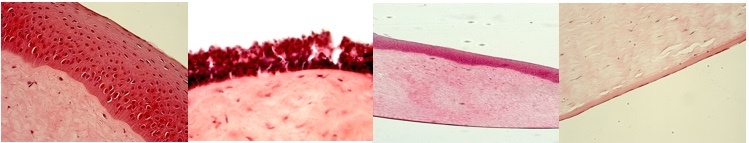

1.2. Prueba EpiSkin test para corrosión cutánea. NORMA REGULADORA OECD TG 431

1.3. Prueba Episkin test para irritación cutánea. NORMA REGULADORA OECD TG 439